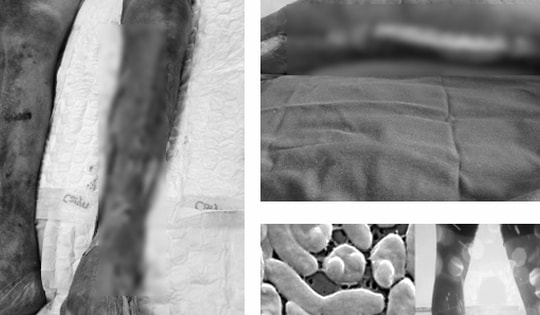

GĐXH – Tổn thương ban đầu của bệnh nhân là ở vùng bàn chân quanh vết thương hở, sau vài giờ lan nhanh lên cẳng chân và đùi trái với triệu chứng đau buốt, thâm tím.

Mới đây một dịch bệnh có cái tên khiến nhiều người sợ hãi đã xuất hiện tại Việt Nam: "vi khuẩn ăn thịt người". Nhìn những biểu hiện ngoài da của người mắc bệnh, nhiều phụ huynh không khỏi rùng mình sợ hãi trước chủng vi khuẩn này. Hiện, Bộ Y Tế đã đưa ra những cảnh báo khẩn về căn bệnh này.

Được đưa vào viện trong tình trạng bị áp xe viêm tuyến nước bọt mang tai nhưng các bác sỹ đã phát hiện cả 3 em nhỏ đã dương tính với Whitmore.